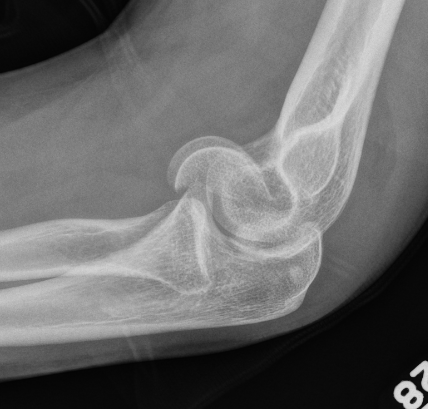

Double arc sign seen on xray

Double arc sign on xray